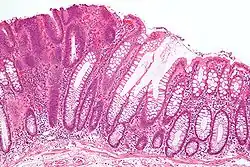

Los tumores vaginales son neoplasias que se encuentran en la vagina. Pueden ser benignos o malignos.[1] Una neoplasia es un crecimiento anormal de tejido que generalmente forma una masa de tejido.[2][3][4] Las neoplasias vaginales pueden ser sólidas, quísticas o de tipo mixto.[5]

Los signos y síntomas pueden incluir una sensación de presión, relaciones sexuales dolorosas o sangrado.[12] La mayoría de los tumores vaginales se localizan durante un examen pélvico. La ecografía, tomografía computarizada y resonancia magnética se utilizan para establecer la ubicación y la presencia o ausencia de líquido en un tumor.[13][14] La biopsia proporciona un diagnóstico más definitivo.[15]